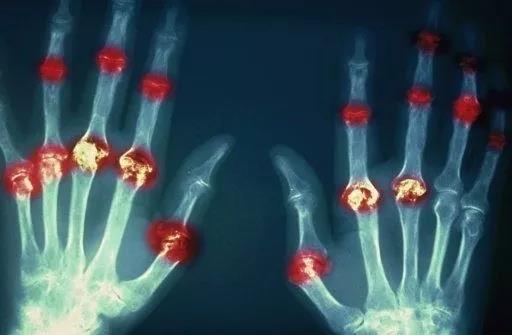

? 類風(fēng)濕關(guān)節(jié)炎

類風(fēng)濕關(guān)節(jié)炎是一種高度致殘的自身免疫性疾病,發(fā)病十年的患者中至少有50%的人失去勞動(dòng)能力。

類風(fēng)濕關(guān)節(jié)炎©Health Same of Flickr

1977年,Baldwin在用骨髓干細(xì)胞移植治療再生障礙性貧血的過程中,意外發(fā)現(xiàn)患者的類風(fēng)濕關(guān)節(jié)炎得到緩解。

2004年,歐洲骨髓移植和抗風(fēng)濕病聯(lián)盟對(duì)60例類風(fēng)濕病關(guān)節(jié)炎移植患者進(jìn)行回顧性分析,這些患者的關(guān)節(jié)破壞都達(dá)到不可修復(fù)程度,生活不能自理,通過干細(xì)胞移植治療后,67%的患者得到明顯緩解。

我國(guó)國(guó)內(nèi)多家醫(yī)院已開展了干細(xì)胞治療類風(fēng)濕性關(guān)節(jié)炎的臨床研究。首例自體干細(xì)胞移植治療類風(fēng)濕關(guān)節(jié)炎在北京協(xié)和醫(yī)院完成。經(jīng)過5個(gè)月隨訪,這些經(jīng)常規(guī)藥物治療失敗且病情發(fā)展迅速的患者,在接受干細(xì)胞移植治療后,癥狀均獲得改善,關(guān)節(jié)腫脹消失,各項(xiàng)檢查指標(biāo)恢復(fù)正常。

解放軍323醫(yī)院2011年的一項(xiàng)臨床研究中,27位患者(對(duì)照組)只使用藥物治療;另外153位患者(細(xì)胞治療組)在藥物治療的基礎(chǔ)上進(jìn)行臍帶間充質(zhì)干細(xì)胞輸注。結(jié)果顯示,治療組DAS28、HAQ 評(píng)分、ACR20較對(duì)照組下降明顯(分值越低,療效越好),Th1/Th2趨于平衡、Treg升高與臨床實(shí)驗(yàn)指標(biāo)及癥狀的緩解直接相關(guān)。